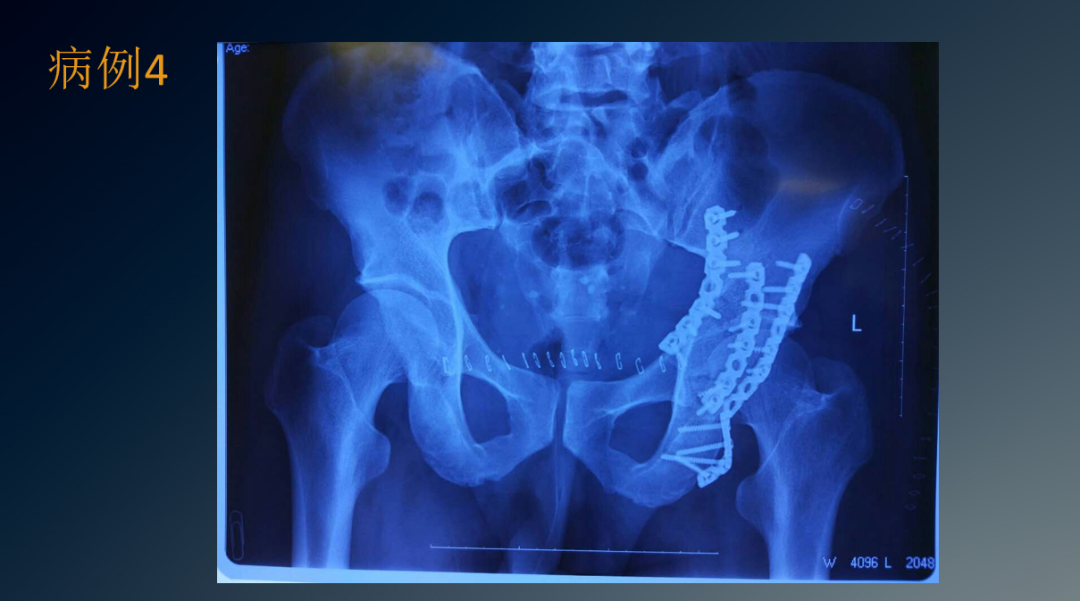

临床病例

治疗盆骨、髋臼骨折常用的手术入路有髂腹股沟入路、K-L入路,前后联合入路,扩大的髂股入路等。髂腹股沟入路主要用于髋臼前壁和前柱骨折,但对于双柱骨折、后壁骨折或累及骶髂关节的髂臼骨折,不建议使用此入路。

K-L入路可直视髋臼后柱的全部侧面,适用于移动的髋臼后柱骨折。扩大的髂股入路对髋臼前柱、关节囊和坐骨大切迹的显露良好,尤其是可显露髋臼顶部的骨折,但因要兼顾前后柱,切口较大,要将臀肌从髂骨上剥离,损伤大出血多。前采用该入路术后出现异位骨化的几率高达85.7%。

因此,该入路目前以较少使用。前后联合入路即K-L入路联合髂腹股沟入路,通过K-L入路可经坐骨小切迹观察四边形区及后柱的骨折复位情况,通过髂腹股沟入路可显露骶髂关节前方,髂骨翼,无名骨,前柱及耻骨联合。采用前后联合入路可减少单一切口所致切口大、肌肉剥离广泛,易损伤血管神经等弊端,可明显减少对髂关节后方组织的干扰,降低异位骨化的发生几率。